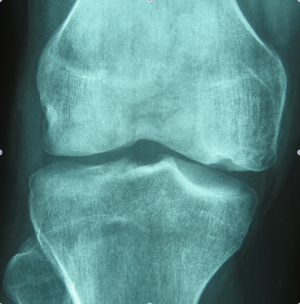

La mayor parte de las lesiones de ligamento cruzado anterior (LCA) ocurren durante la práctica de algún deporte que requiera pivoteo, cambios de dirección, o rotación de rodilla. Los síntomas de una lesión de LCA pueden variar, desde sentir que "se va" o sale de control, que truena o que se presenta una repentina inflamación en la rodilla, hasta la presencia evidente de dolor al caminar. Con una lesión de LCA la rodilla pierde estabilidad, lo que hace que cualquier movimiento de pivoteo repentino resulte muy difícil para el paciente. Este tipo de lesión en la articulación de larodilla también pudiera degenerar en una artritis o daño al cartílago.

Actualmente la lesión de Ligamento Cruzado Anterior (LCA) ya no implica un problema su reparación y aún en deportistas de alto rendimiento pueden retornar a su alto nivel deportivo. La cirugía sin embargo, requiere de alta precisión para su éxito, por lo que requiere de una alta experiencia por parte del cirujano ortopedista. El procedimiento se realiza por tres incisiones, dos de 4 mm y una de 1 a 2.5 cm, por una de las incisiones menores se introduce la cámara con la que se revisa toda la articulación, por otra de las pequeñas incisiones se introducen los instrumentos necesarios y por la tercera se obtiene y se tuneliza el nuevo ligamento.

Cuando hay una ruptura de ligamento este hay que reemplazarlo de dos formas, ya sea utilizando un tendón de banco de tejidos o un tendón del mismo paciente que se obtiene de la misma rodilla lesionada. La ventaja de reemplazar el ligamento cruzado por injerto de banco de tejido es que la cirugía resulta un poco menos dolorosa y más rápida que hace que la rehabilitación sea más rápida.